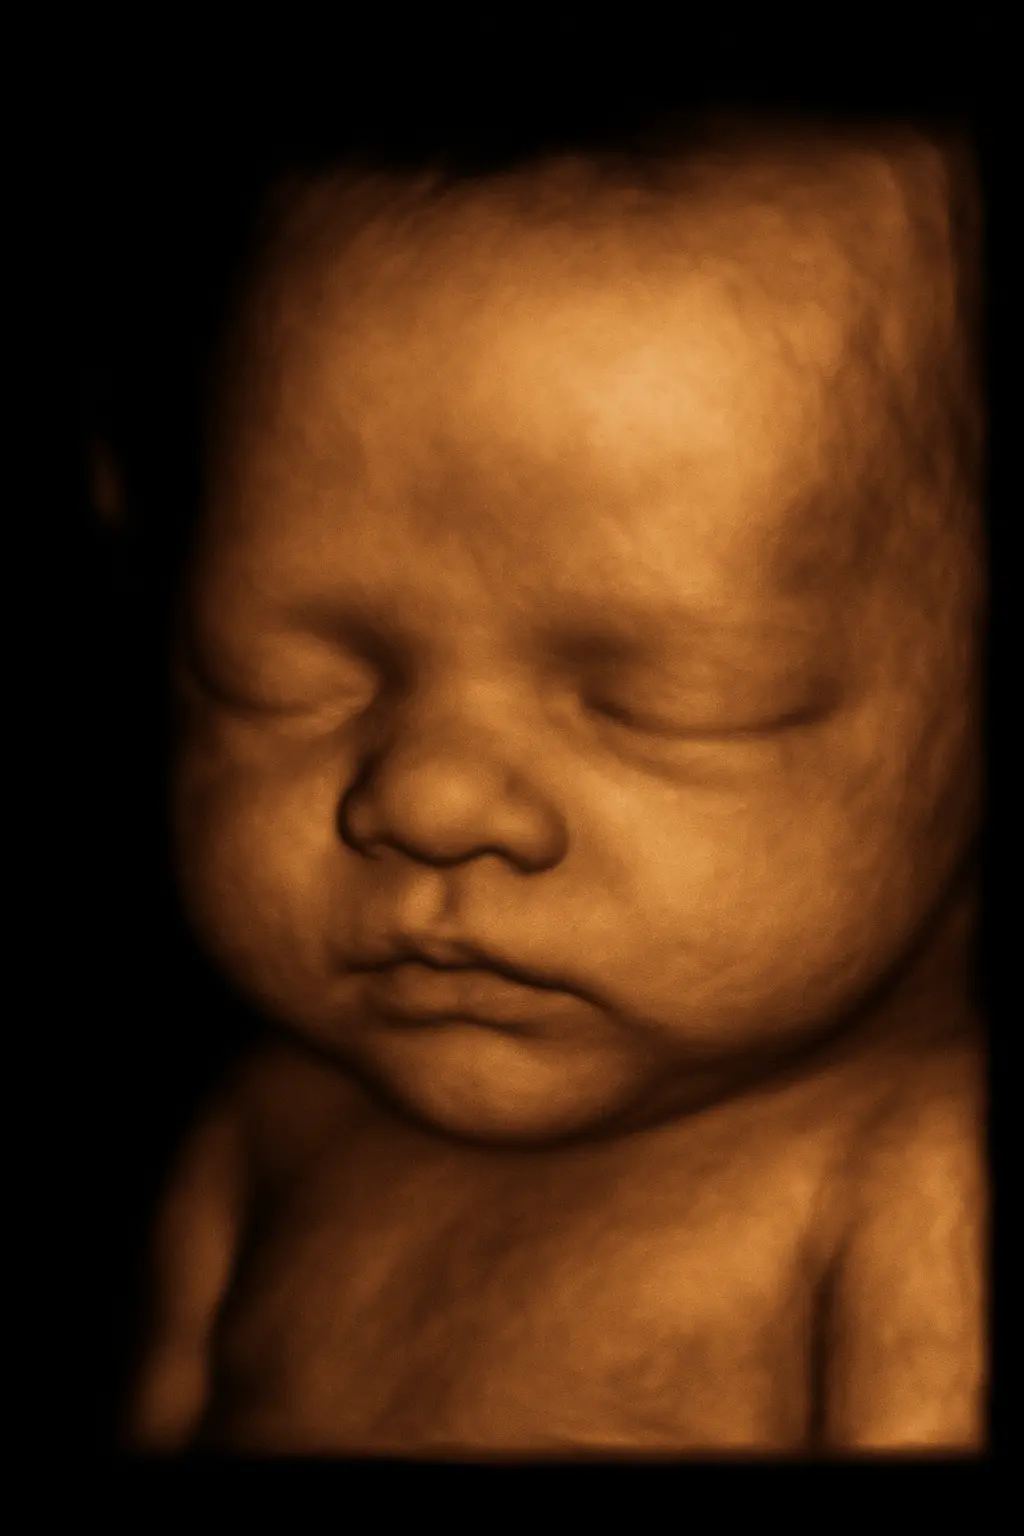

Estudio de ultrasonido obstétrico 4D en León, Gto. - EcoScan

Ultrasonido obstétrico / 4D

Control del embarazo con imagen 2D y 4D.